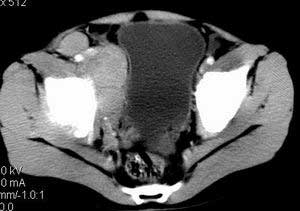

| 患者,男,9岁,因右下腹包块入院,血象不高,不规则发热,常超40度。 平扫: ![]() ![]() ![]() ![]() ![]() ![]() ![]() ![]() ![]() ![]() ![]() ![]() ![]() ![]() ![]() ![]() ![]() ![]() 增强: ![]() ![]() ![]() ![]() ![]() ![]() ![]() ![]() ![]() ![]() ![]() ![]() ![]() ![]() jiajie发言:骶椎右前区不规则软组织肿块,边缘光整,密度均匀,增强后均匀强化,右腹股沟区可见肿大淋巴结,临床有时发热,考虑淋巴瘤,儿童盆腔肿瘤应与神经母细胞瘤和横纹肌肉瘤鉴别。 longzhanghui发言:印象:盆腔右后壁不规则软组织肿块,并向前延伸.似为多个肿块融合,呈中等强化.初步考虑淋巴瘤. 听蝉观竹发言:右侧髂内、外组淋巴结肿大,从其形态和融合的情况看,同意大家意见-----考虑恶性病变,但是9岁男孩还要注意检查睾丸情况,有无隐睾? 常常类似情况是隐睾发生精原细胞瘤淋巴结转移,这个病例也要注意这一点!!! 广东凌发言:大家好,在这里我想说一下个人观点,我建议上传图片的同志能否辛苦一点就是把病史和图片都上传完整一点,比如这个病人的腹膜窗,并且这个病人的肠道的准备也是不怎么好,就从现有的质料看:病灶属于淋巴结肿大当无大的争议,有融合趋势,其内无坏死,边缘强化为主,故考虑:淋巴瘤!建议用腹膜窗看一下和肠道的关系! 阿圣发言:病灶属于淋巴结肿大当无大的争议,有融合趋势,其内无坏死,边缘强化为主,故考虑:淋巴瘤 结果是:淋巴瘤 病例来源:ct762。由宁静致远发布: http://www.radinet.com.cn/forum_view.asp?forum_id=4&view_id=2182 |